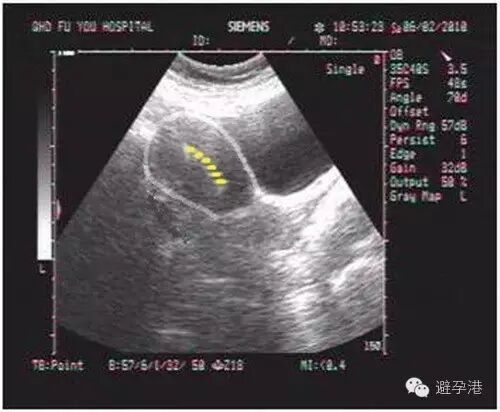

2.分辨率高超声仪器,在子宫肌壁间可见一稍强光点,为吉妮致美线结。

吉妮致美环怎么样吉妮致美节育器超声图像解读_https://www.jmylbn.com_新闻资讯_第4张

吉妮致美环怎么样吉妮致美节育器超声图像解读_https://www.jmylbn.com_新闻资讯_第5张